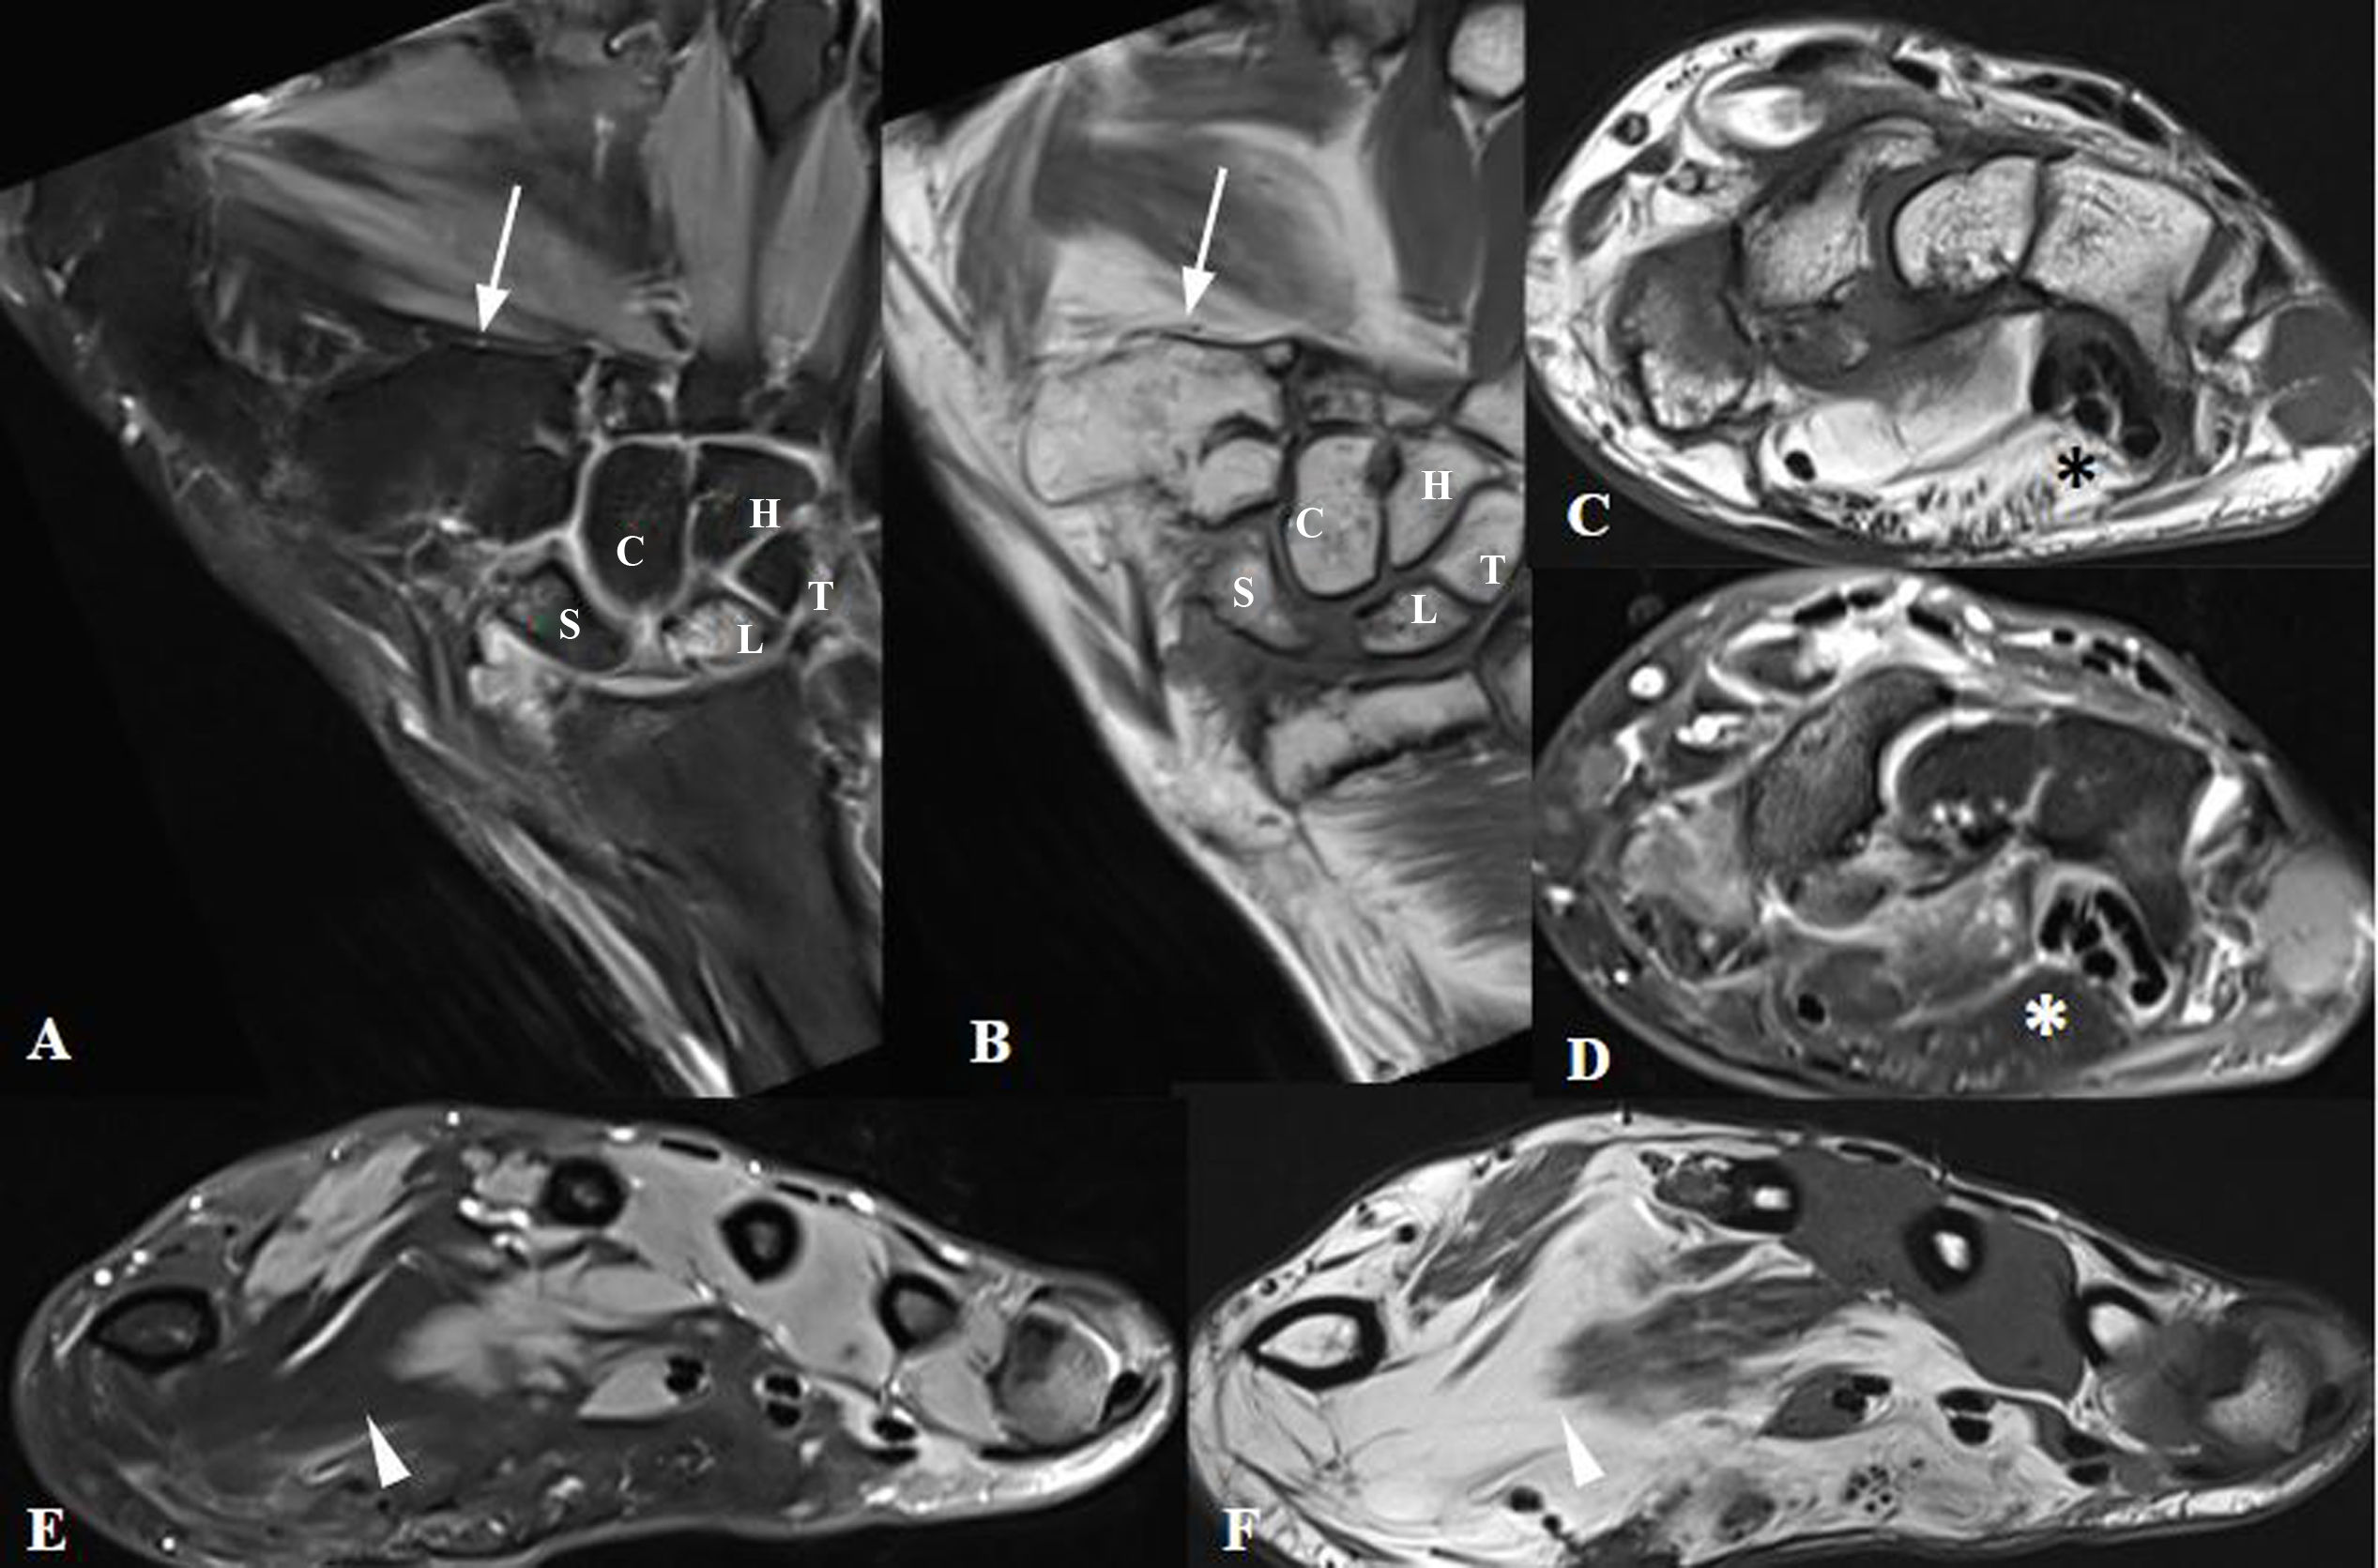

Lipomatosis of nerve (LN) is a rare condition characterised by fibroadipose lesions affecting the peripheral nerves. It presents a complex clinical challenge, often associated with macrodystrophia lipomatosa. Various imaging techniques, specifically magnetic resonance imaging (MRI) and ultrasound (US), are crucial for its diagnosis and precise monitoring. On MRI, LN appears as a lesion displacing surrounding structures, presenting as hypointense cable-like nerve bundles. On US, it has a ‘lotus root-like’ appearance. The wide range of clinical presentations of LN and the extensive array of differential diagnoses underscore the need for individualised diagnostic and treatment strategies. The aim of this article is to provide a thorough review of LN through illustrative images.